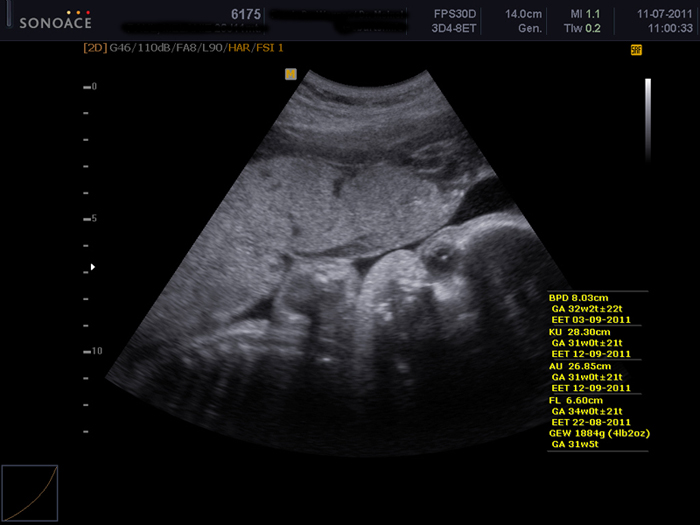

Letzte Woche stand der letzte Ultraschall an. Der kleine Scheißer ist jetzt schon so groß, dass er kaum noch aufs Foto passt. Hier sieht er aus wie ein Alien. :D